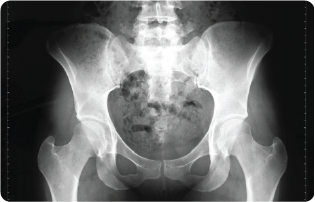

AOANJRR milestone–one million hip replacements recorded

This achievement marks an extraordinary milestone in the Registry’s history, reflecting now 25 years of comprehensive data collection and analysis.